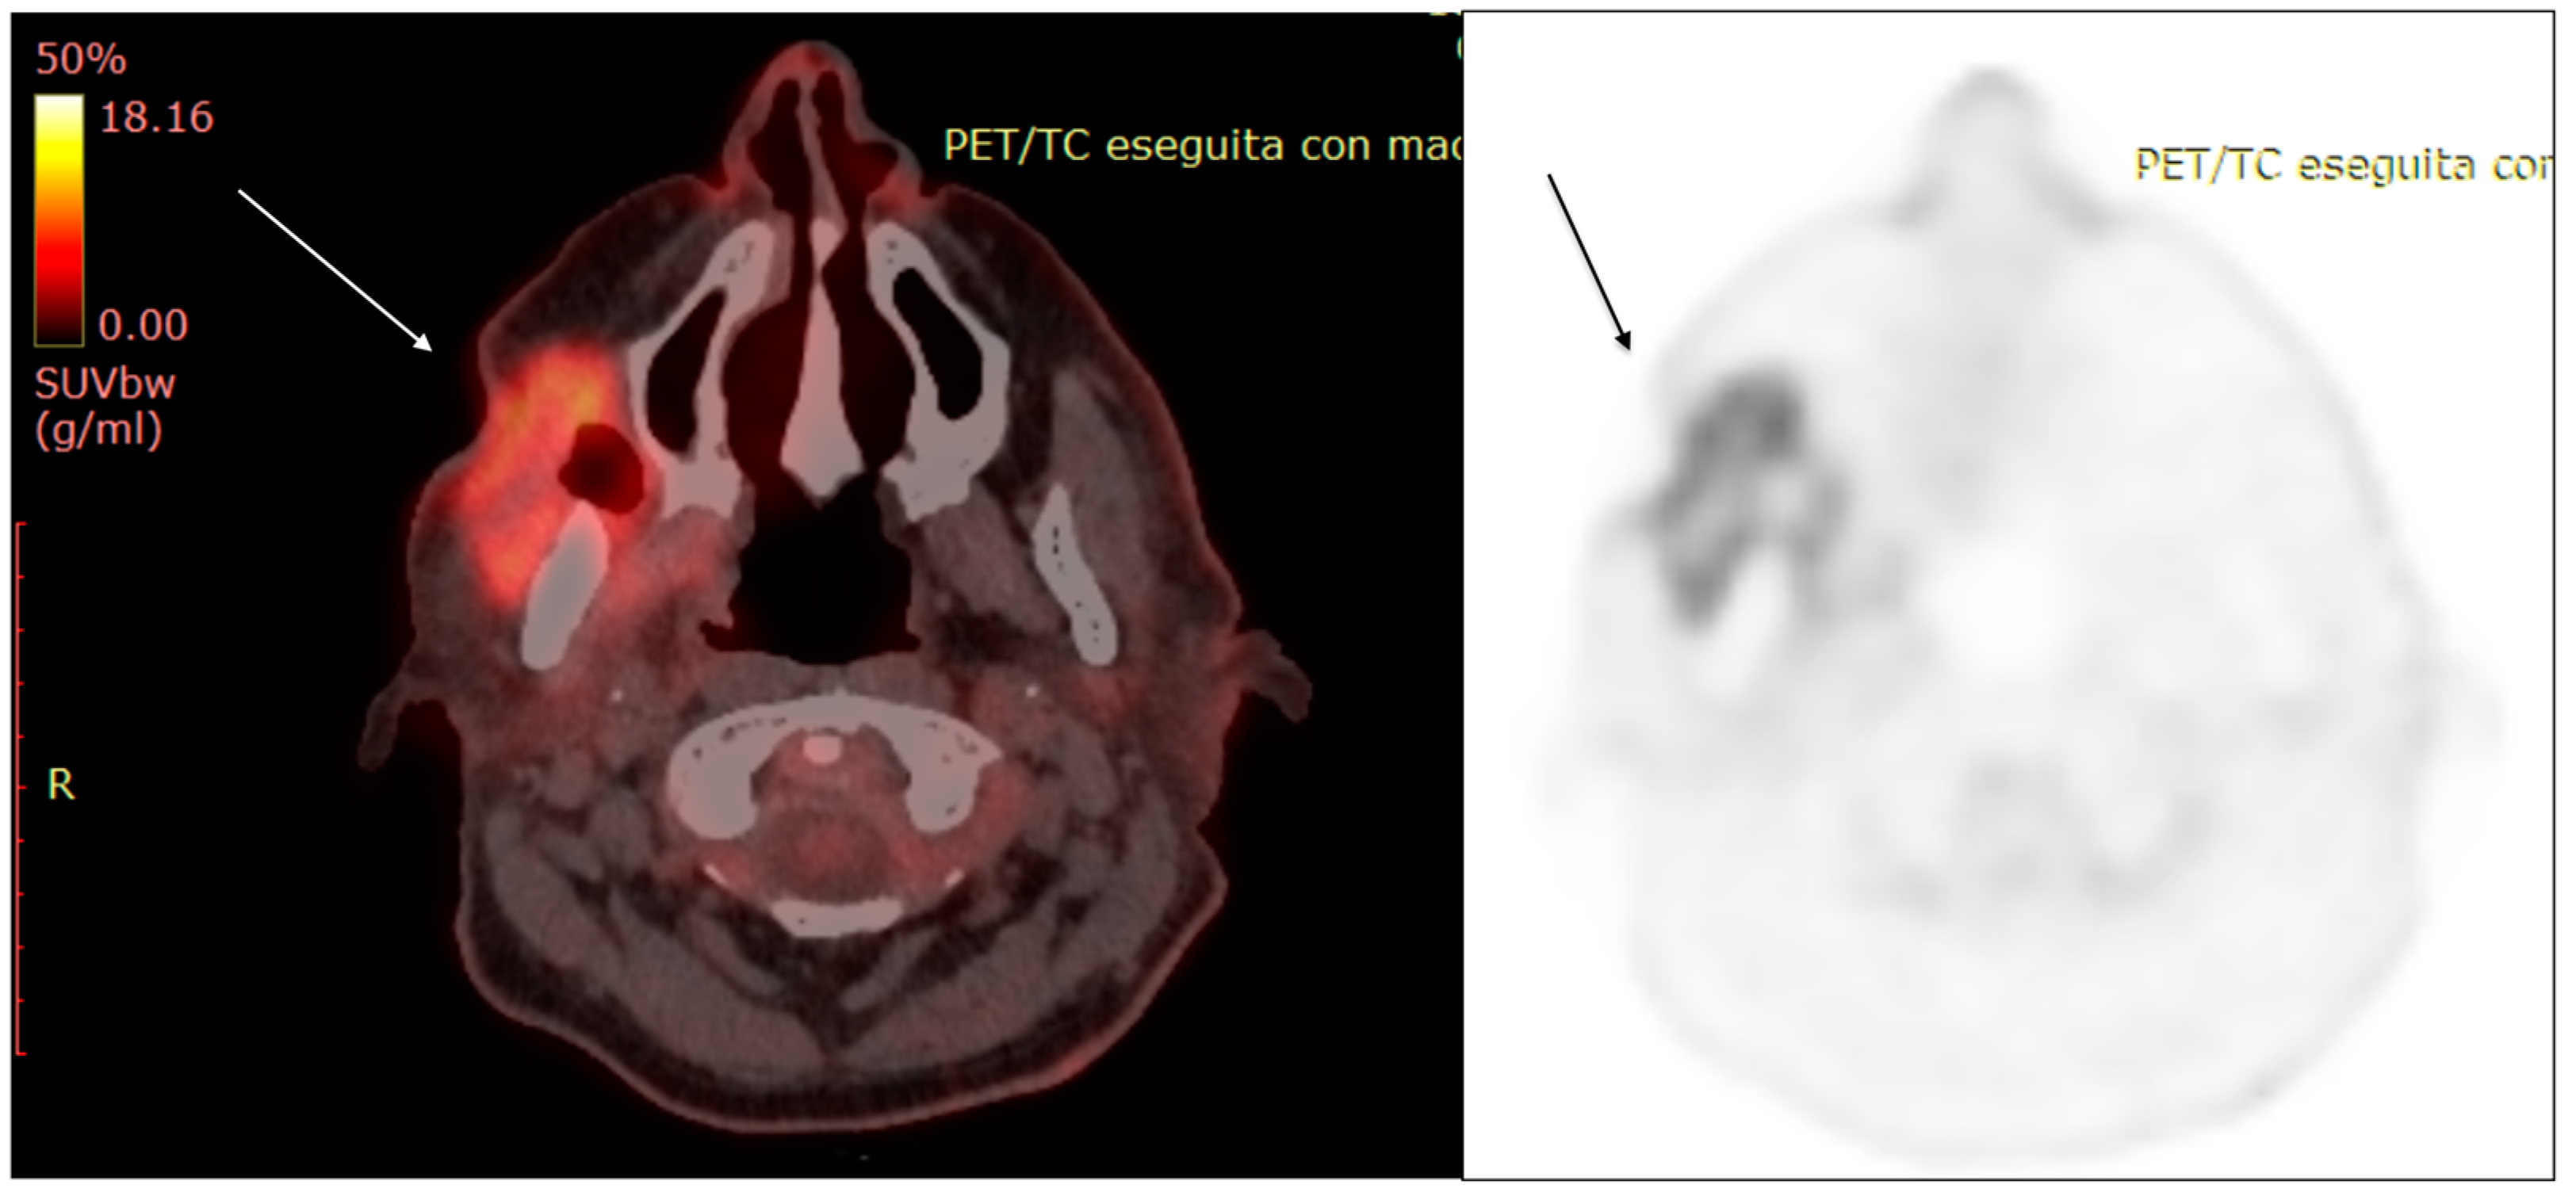

2. Diagnostic Imaging and Non-Melanoma Skin Cancer

3. Diagnostic Tools and Non-Melanoma: Staging and Surveillance